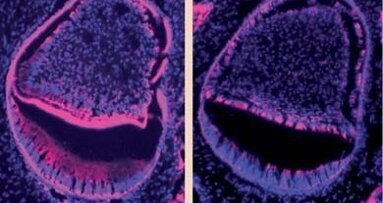

Naukowcy odkryli, że pacjenci, którzy otrzymali leczenie hDPSC mają więcej pozytywnych efektów niż druga grupa kontrolna, a także znacząco większe ukrwienie zęba. Naukowcy odkryli, że wszczepione komórki macierzyste regenerują różne składniki miazgi zębowej, w tym komórki wytwarzające zębinę, tkankę łączną i naczynia krwionośne.